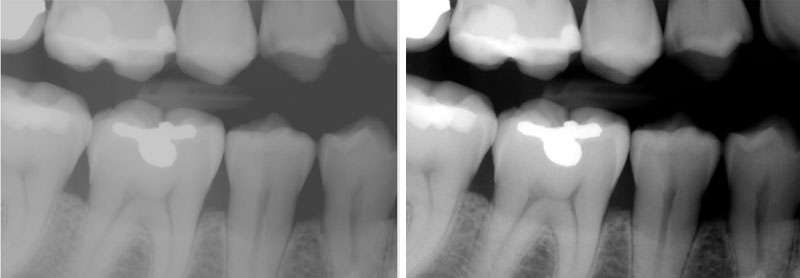

Another best practice to help increase the diagnostic value of an X-ray is adjusting the contrast. Interestingly, an X-ray image can be exposed correctly yet still have too high or too low contrast.

Think of your radiograph as being comprised of dots in varying shades of black, gray, and white on a spectrum. For images that are too high contrast, there are too many dots at the far ends of the spectrum, clustering too close to the black and white areas. X-rays that have too high contrast can prevent you from seeing detail in the gray gradients of your X-ray. Conversely, if an X-ray has too low contrast, the dots are clustered closer to the middle gray area of the spectrum, not offering enough detail in the lightest and darkest areas of the X-ray. See below for the default original image (left) and the adjusted image (right).

Your staff can use imaging software like cloud-enabled Apteryx XVWeb to adjust the contrast until there’s a good balance across the spectrum of colors so you can visualize the darkest areas, the lightest areas, and all areas in between.